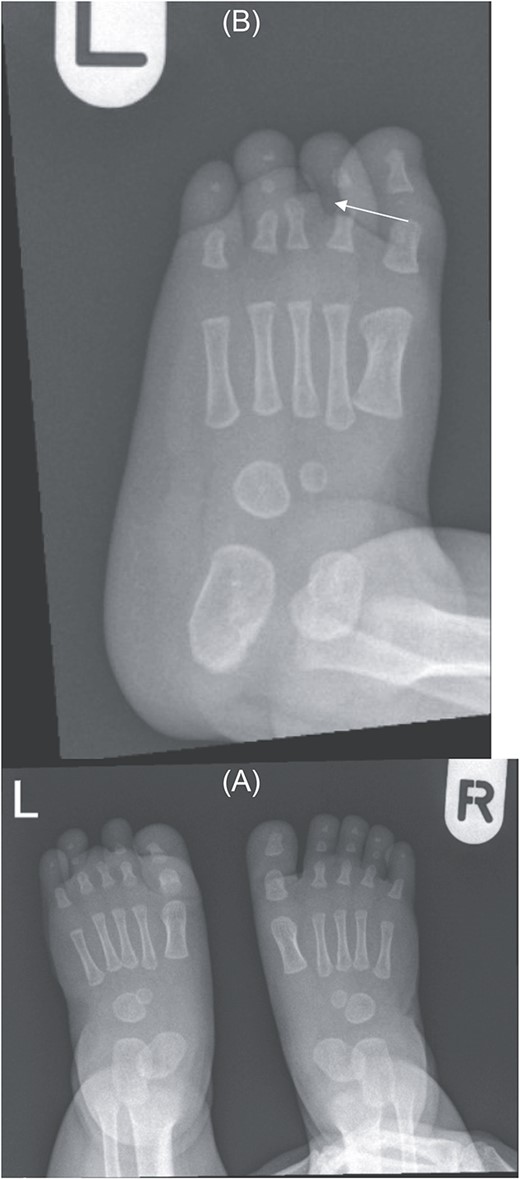

Physical exam showed brachymetatarsia—hypoplastic left third toe with no visualization of the whole digit and absence of toenail (Fig. 1) The rest of the hand and right foot digits appear unremarkable. Hypoplastic left third toe appears nontender, no redness, no swelling, no discharge, and no cysts.

(A) Bilateral feet with normal right foot and left foot (arrow). (B) Hypoplastic left third toe with no visualization of the whole digit and absence of toenail (arrow).

Foot X-ray confirms hypoplastic left third toe with no visualization of middle and distal phalanges — suggesting a very rare variant of brachydactyly (type B) (Fig. 2).

(A) Bilateral feet X-ray with normal right foot bone anatomy and left foot X ray. (B) No visualization of third toe middle and distal phalanges (arrow).